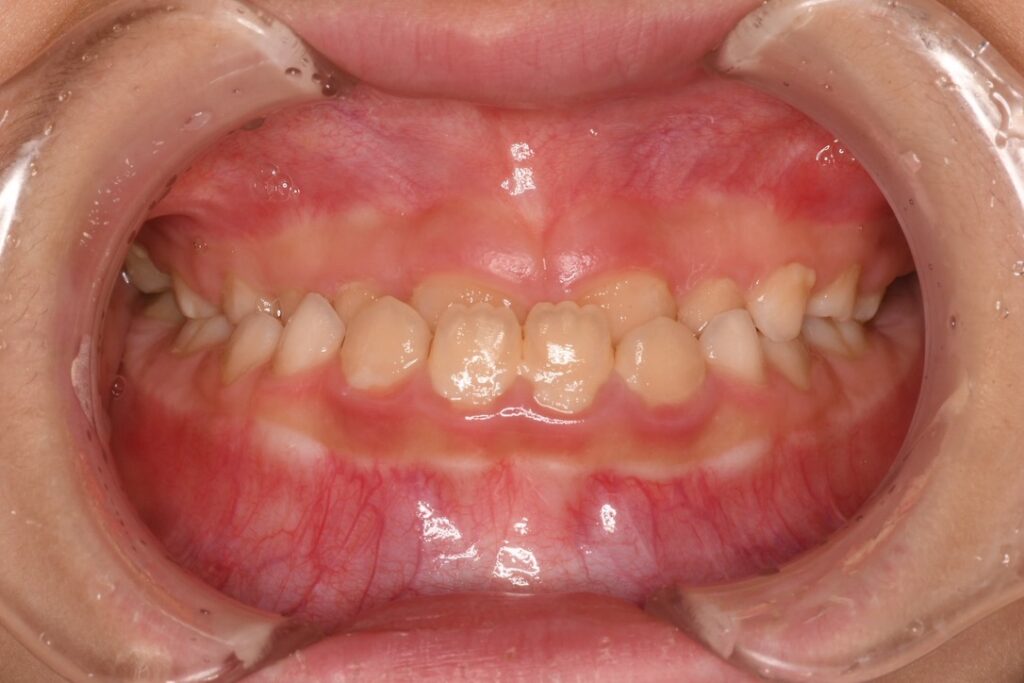

治療前の状態

初めて来院されたとき、この女の子は下の前歯が上の前歯より前に出ていました。

これは典型的な「受け口(反対咬合)」という状態で、そのままにしておくと あごが正しく成長できない可能性 があります。